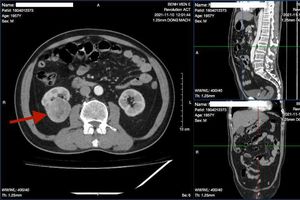

Các bác sĩ đă ứng dụng công nghệ in 3D trong việc phẫu thuật cắt u thận, tạo h́nh bể thận trong xoang cho một trường hợp bệnh nhân nam 64 tuổi được chẩn đoán ung thư thận phải cực giữa.

Các bác sĩ tại Khoa Phẫu thuật Thận tiết niệu & nam học (Bệnh viện E) vừa ứng dụng công nghệ in 3D trong phẫu thuật cắt u thận, tạo h́nh bể thận trong xoang thành công cho trường hợp bệnh nhân nam 64 tuổi bị ung thư thận phức tạp.

Ngay tại Việt Nam, thời gian qua đă có sự ứng dụng in 3D trong việc ghép xương, thay khớp tại bệnh viện Tâm Anh, bệnh viện Vinmec… đem lại nhiều thành quả rất đáng ghi nhận.Trong tháng 11/2021 vừa qua, dưới sự ủng hộ và tạo điều kiện của ban giám đốc bệnh viện E, các bác sĩ tại Khoa phẫu thuật Thận tiết niệu và nam học đă ứng dụng công nghệ in 3D trong việc phẫu thuật cắt u thận, tạo h́nh bể thận trong xoang cho một trường hợp bệnh nhân nam 64 tuổi được chẩn đoán ung thư thận phải cực giữa.

Tuy nhiên, áp dụng tiến bộ của khoa học công nghệ, cùng với sự nghiên cứu, ứng dụng những kỹ thuật mới, TS.BS Nguyễn Đ́nh Liên - Trưởng khoa Phẫu thuật thận tiết niệu & nam học Bệnh viện E đă thực hiện in 3D quả thận kèm khối u và lên phương án phẫu thuật cho bệnh nhân.

Nhờ có hệ thống chụp cắt lớp vi tính đa dăy, kết hợp với công nghệ in 3D; các bác sĩ đă tính toán với độ chính xác gần như tuyệt đối sự xâm lấn khối u, cấu trúc mạch máu… qua đó các bác sĩ đă có phương án cắt trọn vẹn khối u và tạo h́nh bể thận, giữ lại quả thận cho người bệnh.Ứng dụng in 3D với độ chính xác gần như tuyệt đối, người bệnh giống như được mổ tới hai lần: Lần một là sự mổ chi tiết qua mô h́nh 3D trên máy tính, lên phương án chi tiết, sát với thực tế nhất. Cho nên trong quá tŕnh mổ thực tế trên người bệnh sẽ diễn ra thuận lợi hơn, người bệnh có khả năng giữ được phần thận lành được cao nhất khi kết hợp với sinh thiết tức th́ diện cắt quanh u.